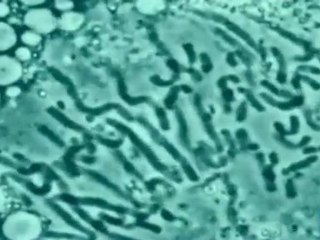

La enfermedad de Alzheimer es una de las "plagas" de la sociedad moderna. El número de personas que la padecen directa o indirectamente, así como el enorme gasto sanitario que produce, son temas recurrentes en las páginas de información general. Durante los últimos años hemos asistido a una minirrevolución científica con relación a esta enfermedad. Gran parte de esta revolución es debida al "éxito" de la estrategia genética para el estudio de la enfermedad y comenzó con la descripción de mutaciones en el gen de la proteína amiloide, el principal componente de una de las lesiones a través de las que se manifiesta la enfermedad. A partir de ese momento, un creciente número de laboratorios ha ido expandiendo nuestro conocimiento sobre esta proteína y sobre los mecanismos que parecen estar en juego en la enfermedad.